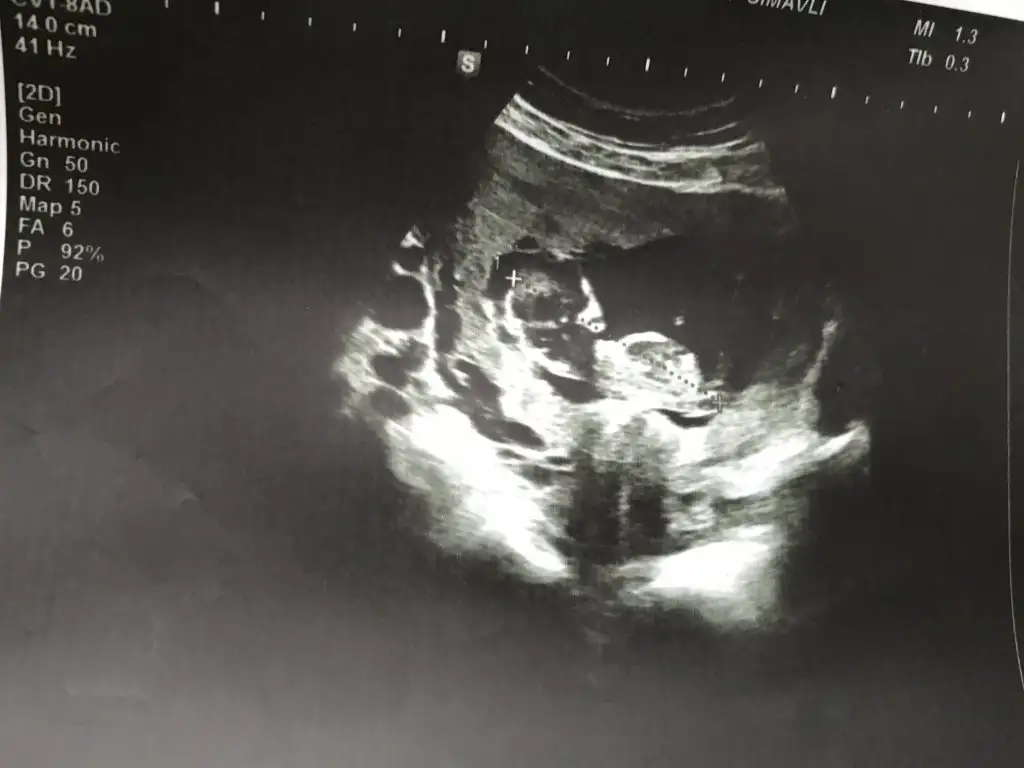

Bide bunlara bak bakalım cnm12hafta 6günlükEki Görüntüle 2585761

13 haftalık :) doktor söylemedi cinsiyetini yanıltıcı olabilir dedi. Tahmini ni bile söylemediKaç haftalık sanki kız gibi 12 hafta paylaşın

Başka usg varmı teyit edim13 haftalık :) doktor söylemedi cinsiyetini yanıltıcı olabilir dedi. Tahmini ni bile söylemedi. Teşekkür ederim